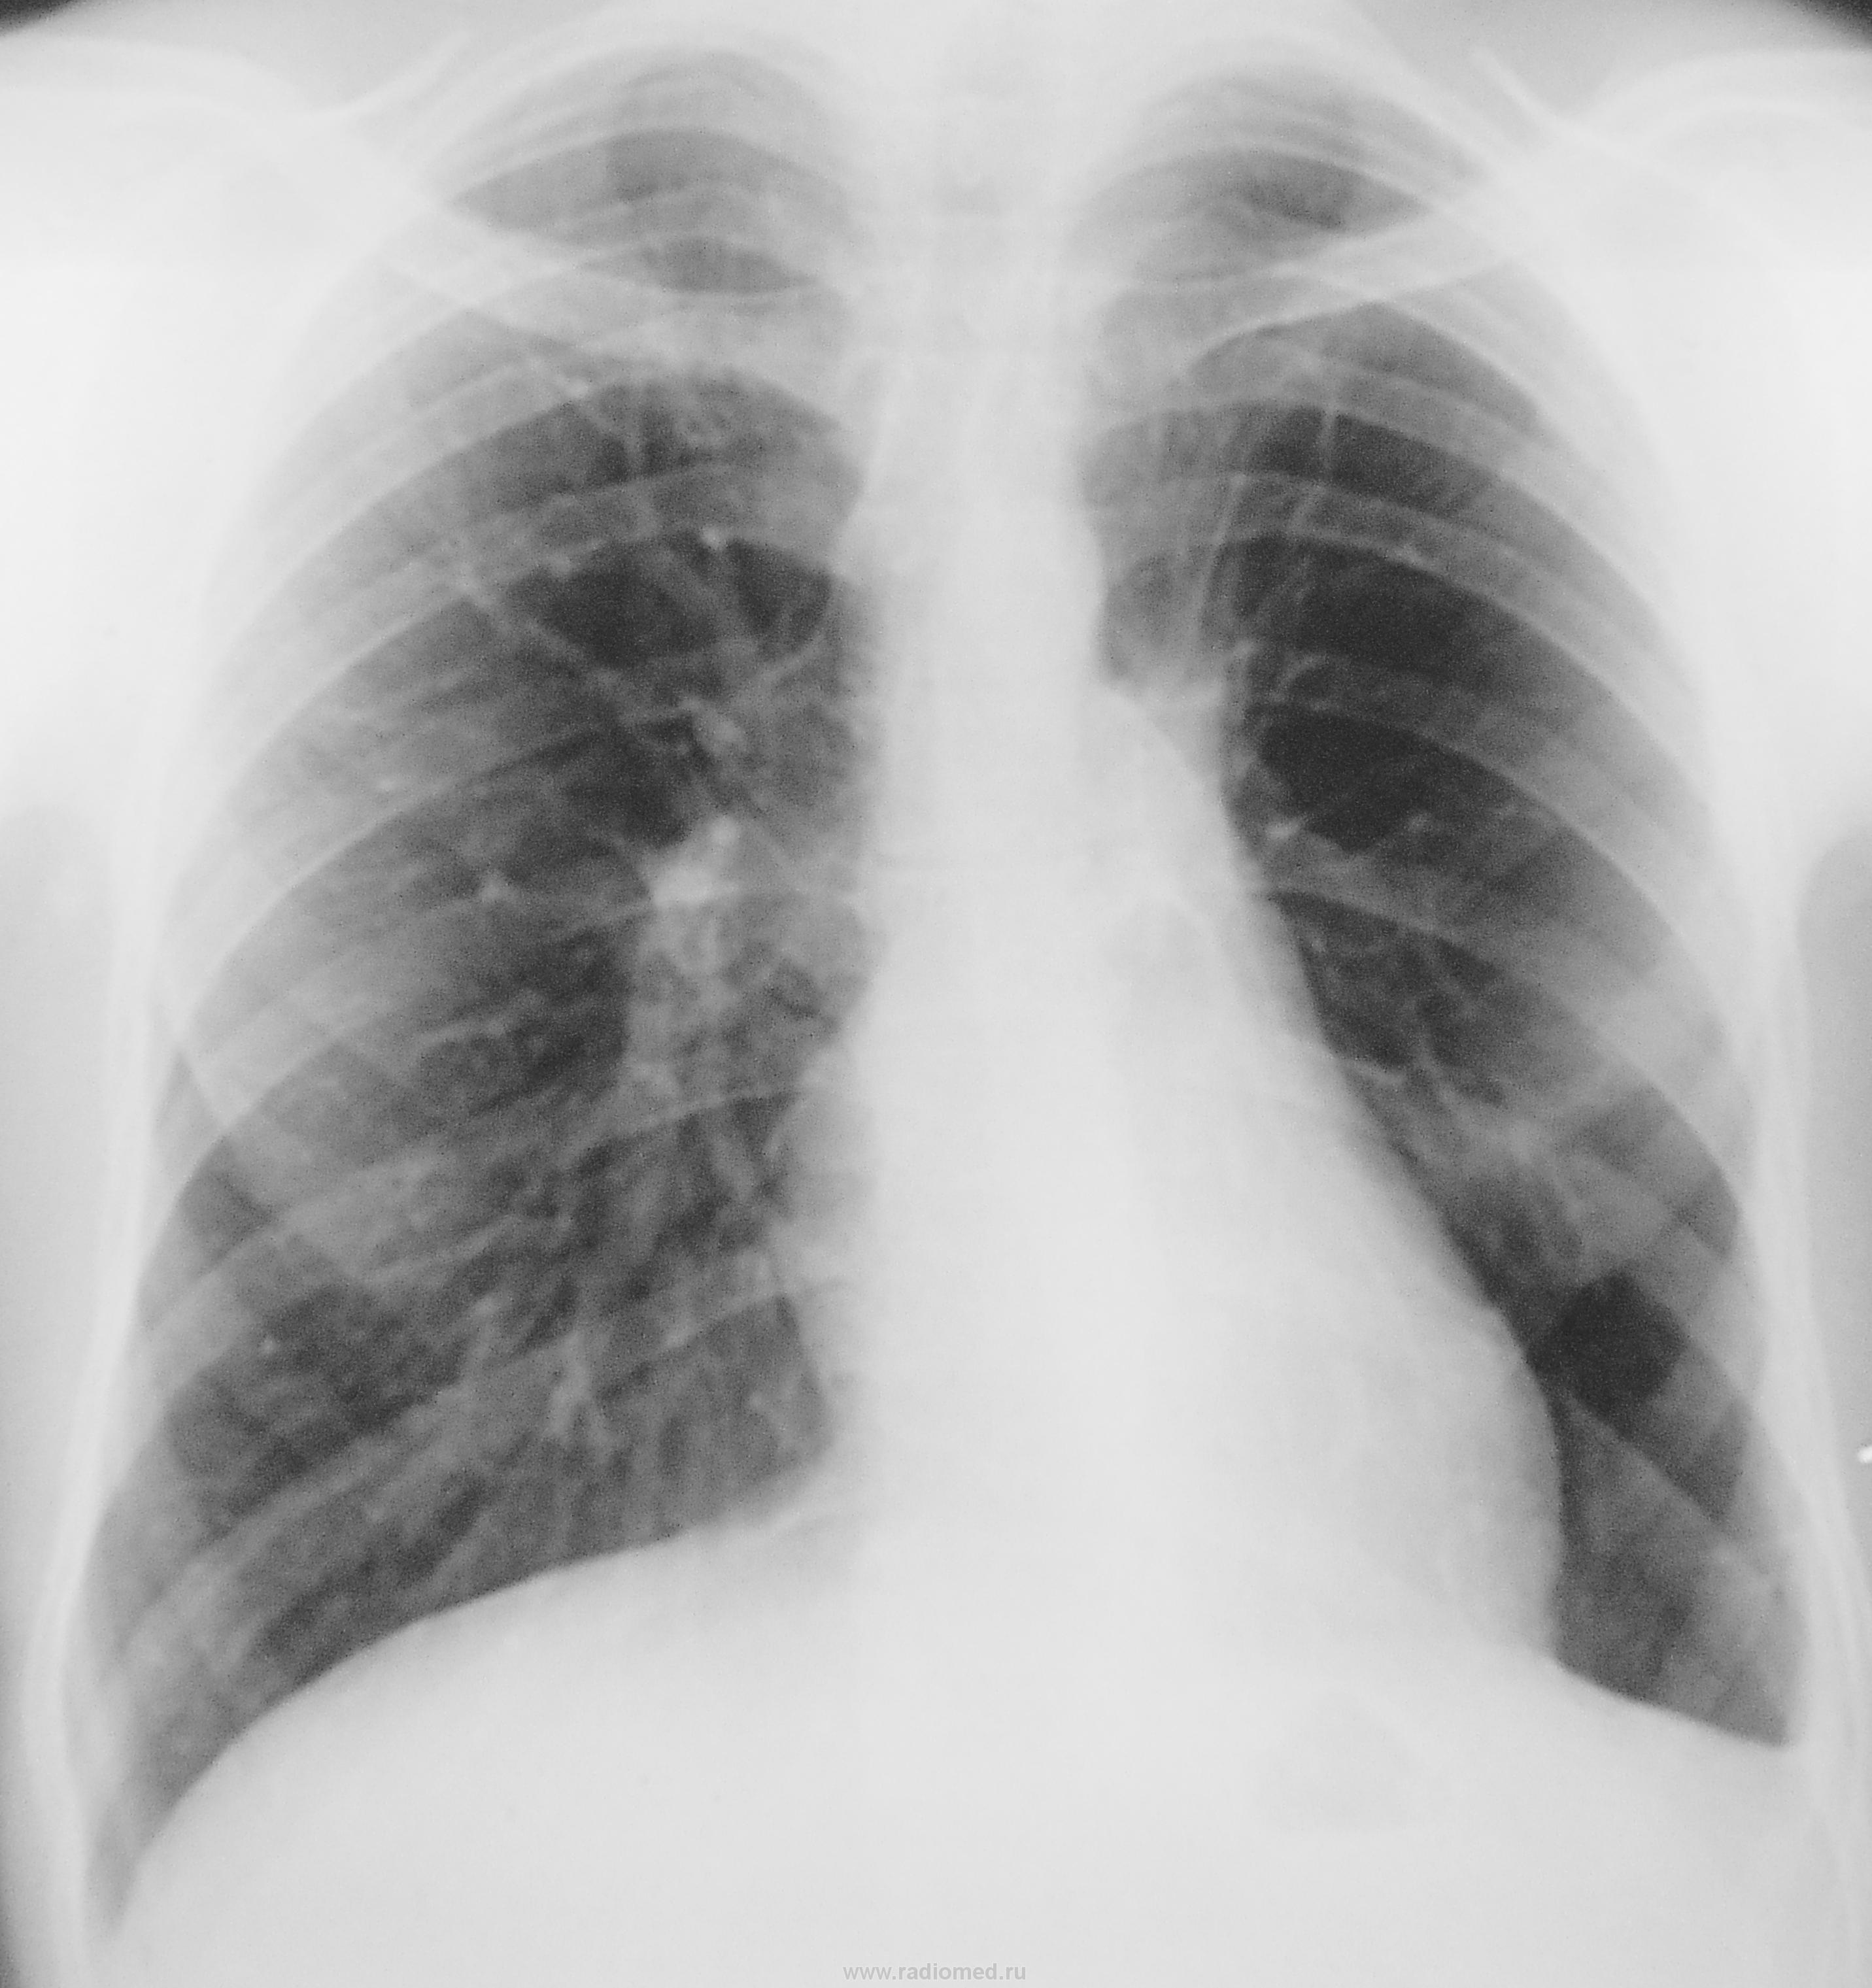

"Флюшка" полтора года тому назад

Приложения:

1.dscn0649.jpg2.dscn0649a.jpg3.dscn0650.jpg4.dscn0650a.jpg

Возраст? В динамике отчетливое разрежение с/рисунка слева в среднем л/поле, сгущение(?) в верхних (парамедиастинальных) отделах, смещение корня кверху. Резко выраженная митрализация сердечной тени. Если это не ТЭЛА (при отсутствии клиники!), то в первую очередь, с моей точки зрения, нужно исключать центральный обЪемный процесс. Нужна боковая и, по-хоршему, исходя из ее данных ТМГ.

Обеднение рисунка было и раньше. Огромное буллезное поражение или все-таки гипоплазия.

Два года тому назад.

1.dscn0651a.jpg2.dscn0652.jpg3.dscn0653.jpg4.dscn0654.jpg5.dscn0655.jpg6.dscn0656.jpg

воздушная киста.во как средостение смещало!